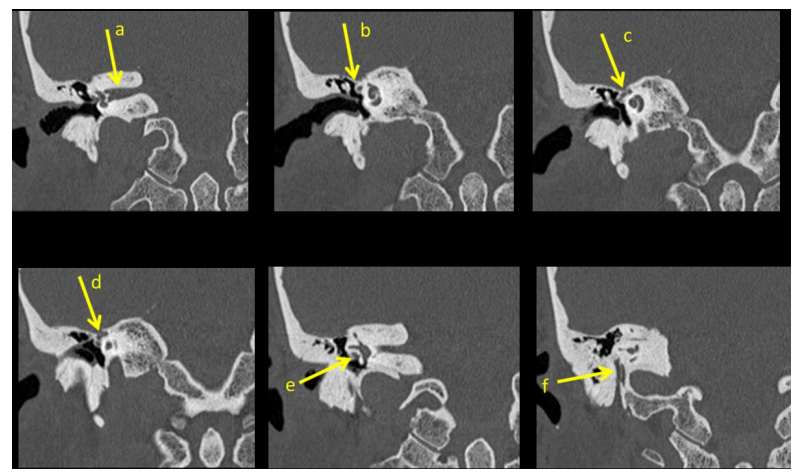

怀疑面神经在颞骨内病变时还需要拍颞骨CT薄扫轴位+冠状位,毕竟MRI对骨性结构看得不清楚。在颞骨CT骨窗下,神经和其他软组织看起来密度是差不多的,所以主要通过骨性结构辨别神经。脑子里有了面神经走行的大致位置,CT上辨认面神经就比较简单了,见图4加强一下。

图4

a是向外前走的颅内段(内听道段)。b所在冠状位是a向前一个冠状位,b是突然变瘦的部分,也就是迷路段。再向前的冠状位可见,c、d小孔里的是膝状神经节,其中c里貌似有两个孔,内侧的那个就是分出来的岩浅大神经。e所在冠状位是a向后的冠状位,e是水平走行的鼓室段,所以冠位上是一个点。f是乳突段,垂直走行,冠状位成向下垂直线。面神经走行就是这么蛇一样弯弯曲曲。